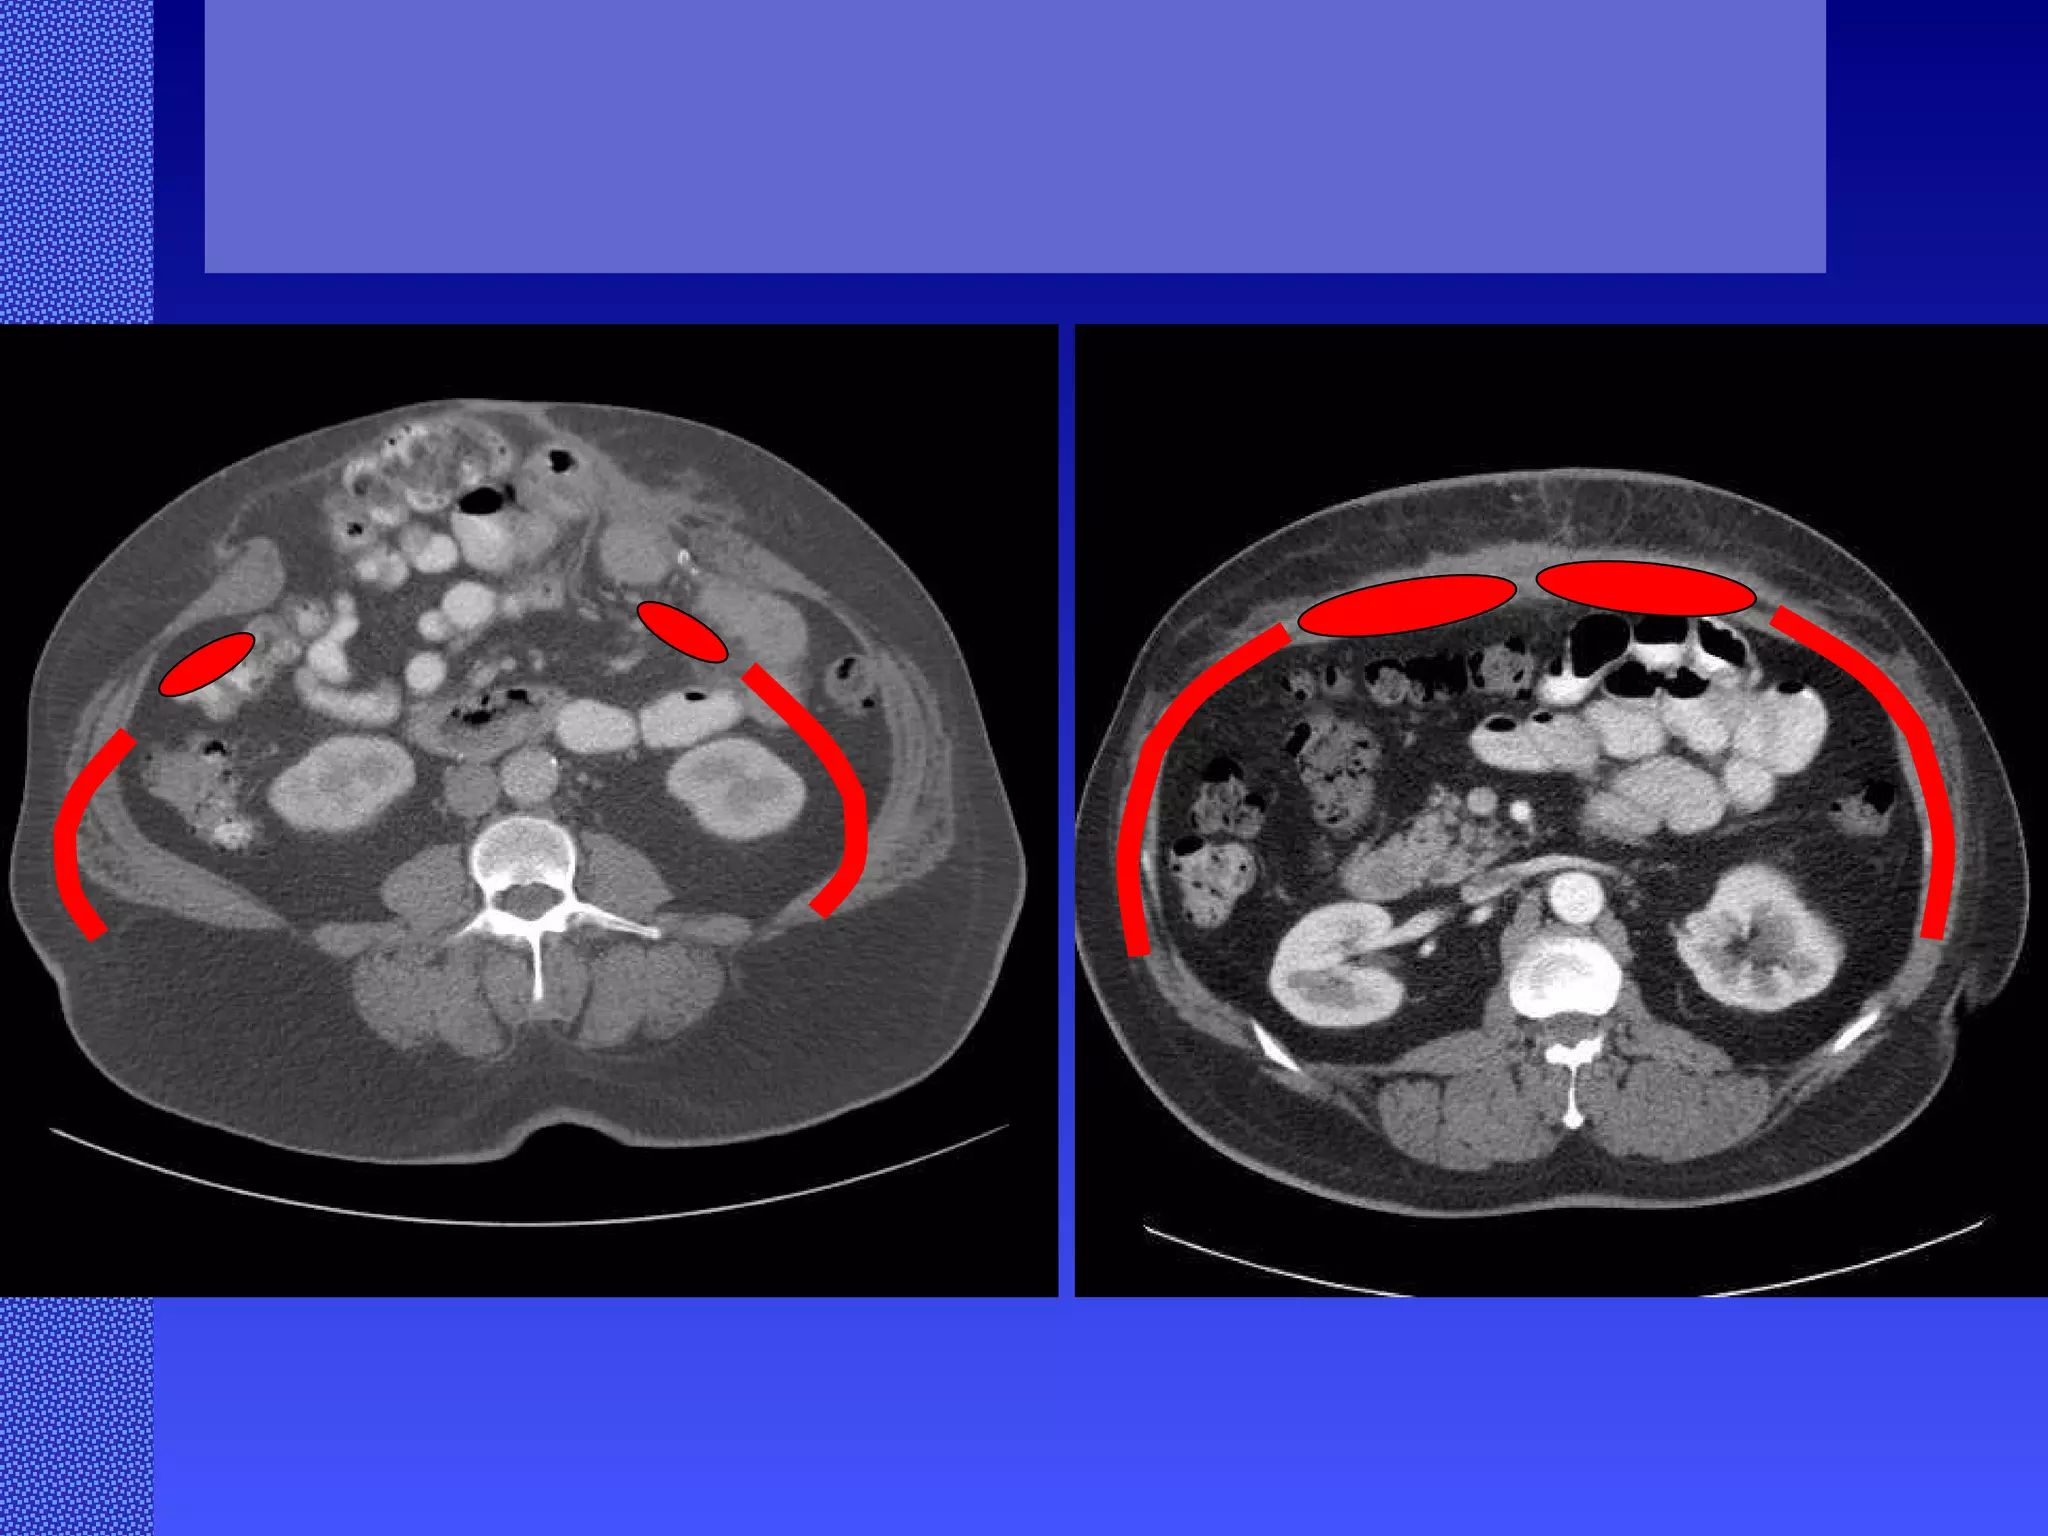

Abdominal Wall Reconstruction: Lessons Learned From 200 “Components Separation” Procedures. Ko, J, MD; Wang, E, PhD; Salvay, D, MS; Paul. B, BA; Dumanian, G, MD ArchSurg/vol 144 (No. 11), Nov 2009  www.archsurg.com Figure 3 A 41-year old man with a history of a perforated appendix treated through a midline incision who later developed an incisional hernia. A, Preoperative oblique view after a hernia repair with polypropylene mesh by another surgeon. B, Preoperative computed tomography scan demonstrating the small bowel herniating to the right of the polypropylene mesh, with wide displacement of the rectus abdominus muscles. C, Six-month postoperative oblique view demonstrates restoration of abdominal wall continuity. D, Postoperative anterior view demonstates stable midline closure and bilateral transverse subcostal incision scars.  Need photos